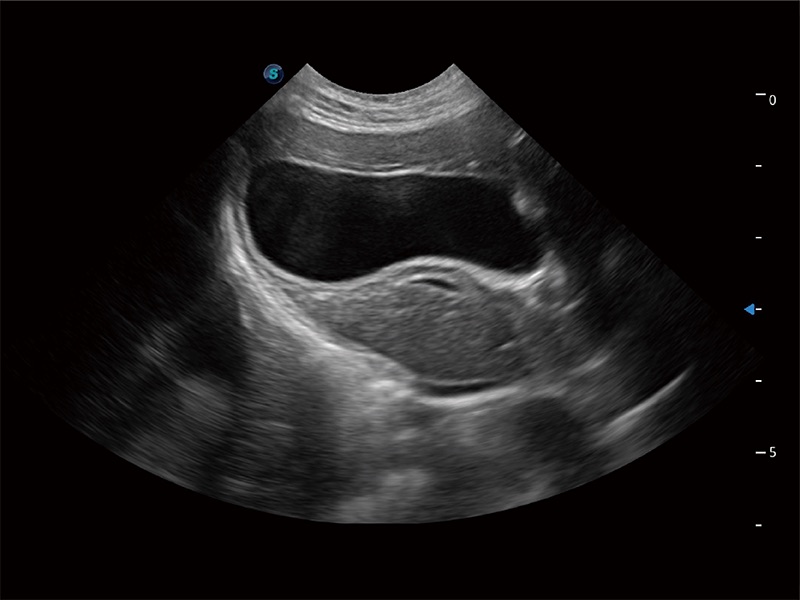

ProPet 80 配备了丰富的心脏探头群、先进的成像技术和专业的心脏测量工具,可帮助动物医生为不同体型和生理结构的动物提供心脏和心肌功能的全面评估。

能够增加心肌组织与血流之间的区别。对于心脏扫查困难的动物,可提供更好的心内膜边界的显示。